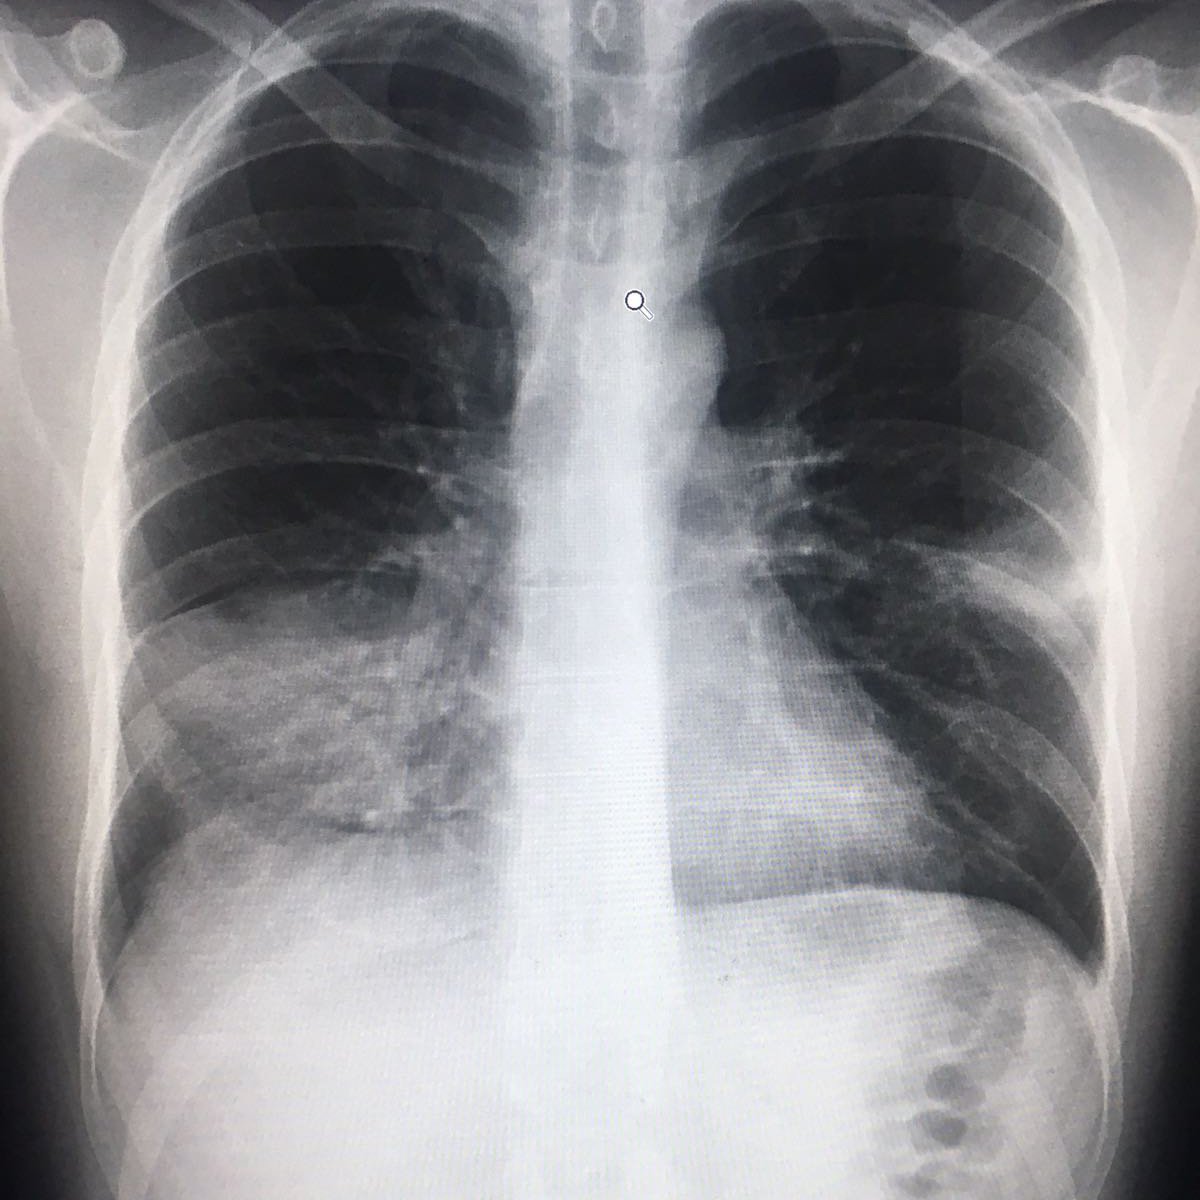

Основная причина госпитализации у большинства наших больных — как раз развитие вирусной пневмонии. У пациентов, госпитализированных в стационар, мы практически в 95-100% случаев видим изменения, соответствующие пневмонии. Изменения разные, в том числе и очень тяжелые. Одна из особенностей вирусной пневмонии — быстрое прогрессирование, вплоть до развития острого респираторного дистресс-синдрома. Это тяжелое состояние, характеризующееся острой дыхательной недостаточностью, требующее перевода пациентов на респираторную поддержку. В том числе и на искусственную вентиляцию легких. Примерно 10% больных от госпитализированных нуждаются в такой процедуре.

Сергей Авдеев: Да, безусловно. Сегодня большой акцент делается на компьютерной томографии легких. Этот метод относится к имидж-диагностике, как и рентгенография. Но компьютерная томография — более точная и специфичная методика выявления изменений в ткани легких по сравнению с обычной рентгенографией. Большинству пациентов с COVID-19 как раз и требуется такая методика. Компьютерную томографию я бы поставил сегодня на первое место среди всех имеющихся методов для подтверждения диагноза. По своей чувствительности она даже превосходит лабораторную диагностику для подтверждения вирусной инфекции. Чувствительность компьютерной томографии превышает 90%.

Сергей Авдеев: Да, отличия существенные. При COVID-19 практически всегда пневмония двусторонняя, расположена по периферии легких (под плевральной оболочкой). На начальных этапах она имеет вид, как говорят рентгенологи, «матового стекла». При прогрессировании изменения становятся более плотными и распространенными. А затем происходит фаза обратного развития — уменьшение размера и плотности легочных инфильтратов.

Сергей Авдеев: Это абсолютно новая болезнь для нас. Данная вирусная инфекция имеет огромный тропизм (свойство действовать на ткани и клетки определенного типа — прим. «Ленты.ру») к альвеолярному эпителию, то есть мишенью для вируса является легочная ткань. Таких вирусов мы раньше просто не видели и не знали. Сейчас в наших клиниках среди госпитализированных с ковидом пациентов почти у каждого есть пневмония — у 95 процентов! Это очень необычное явление.

Сама пневмония протекает по абсолютно разным сценариям. В ряде случаев — без единого симптома. Ни температуры, ни кашля, ни одышки. То есть человек просто не ощущает, что болеет.

Другой сценарий — пневмонии при COVID-19 часто быстро прогрессируют, у пациентов возникает острая дыхательная недостаточность. Это требует использования сложных методов респираторной поддержки, включая искусственную вентиляцию легких.

Да, это одна из особенностей COVID-19. Самый действенный метод — увидеть пневмонию на компьютерной томографии. Чувствительность метода КТ достигает 97 процентов, поэтому он выходит на первый план при диагностике воспалительного процесса.

Если коротко, то при COVID-19 пневмония — двусторонняя, локализация — периферическая. Микоплазменные пневмонии чаще односторонние. Встречаются и двусторонние, однако в этом случае томографические снимки отличаются, изменения в легких иные.

Одно из главных отличий вирусной пневмонии от бактериальной – быстротечность. Ковидное воспаление легких протекает стремительно и агрессивно

Одно из главных отличий вирусной пневмонии от бактериальной – быстротечность. Ковидное воспаление легких протекает стремительно и агрессивно, быстро наступает дыхательная недостаточность.

Если для развития бактериальной пневмонии требуется время – неделя, а то и две, то для вирусной достаточно четырех-пяти дней от начала заболевания. При этом симптомов может не быть вовсе, объясняет пульмонолог.

Бактериальной пневмонии всегда предшествует яркая симптоматика, при ковидной изменения в легких могут опережать симптомы. Человек может чувствовать себя вполне нормально, а часть легких у него уже поражена.

Рентгенологи делят ковидную вирусную пневмонию на четыре стадии, в зависимости от объема поражения легких: это кт-1 (легкая), кт-2 (среднетяжелая), кт-3 (тяжелая) и кт-4 (критическая).

На раннем этапе заболевания, по словам врача, определить вирусную пневмонию можно только с помощью компьютерной томографии. Но если процесс уже достаточно распространен, врачи могут распознать вирусное воспаление легких и с помощью рентгенографии.

КТ на ранней стадии позволяет увидеть те изменения, которые называются синдромом «матового стекла». На снимке видно, что альвеолы как бы затянуты «дымкой». Если бактериальная пневмония проявляется в виде участков уплотнения, очаговых теней, то здесь легкая «дымка» окутывает все ткани альвеол.

Более тяжелые стадии вирусной пневмонии на рентгеновском снимке напоминают, по словам специалиста, «булыжную мостовую».